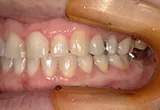

| 年齢/性別 | 70代女性 |

| 主訴 | 左下奥歯に痛みがある、全体的に治したい |

| 治療内容 | 全体的に歯周病やむし歯、根の治療を行い、仮歯を使用して咬合治療を実施。左上、右下、左下の計3本を抜歯し、右上には2本のインプラントを埋入しました。 |

| 治療期間 | 4か月(インプラントのみ) |

| 費用 | 1,116,500円税込 |

| リスク・副作用 | 炎症反応によって術後に腫れや副鼻腔炎が生じることがあります。その程度は、手術の範囲や方法によって異なりますが、多くの場合、時間の経過とともに徐々に治まります。 |